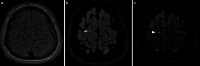

The recently developed effective treatment of primary progressive multiple sclerosis (PPMS) requires the accurate diagnosis of patients with this type of disease. Currently, the diagnosis of PPMS is based on the 2017 McDonald criteria, although the contribution of magnetic resonance imaging (MRI) to this process is fundamental. PPMS, one of the clinical types of MS, represents 10%-15% of all MS patients. Compared to relapsing-remitting MS (RRMS), PPMS differs in terms of pathology, clinical presentation and MRI features. Regarding conventional MRI, focal lesions on T2-weighted images and acute inflammatory lesions with contrast enhancement are less common in PPMS than in RRMS. On the other hand, MRI features of chronic inflammation, such as slowly evolving/expanding lesions (SELs) and leptomeningeal enhancement (LME), and brain and spinal cord atrophy are more common MRI characteristics in PPMS than RRMS. Nonconventional MRI also shows differences in subtle white and grey matter damage between PPMS and other clinical types of disease. In this review, we present separate diagnostic criteria, conventional and nonconventional MRI specificity for PPMS, which may support and simplify the diagnosis of this type of MS in daily clinical practice.